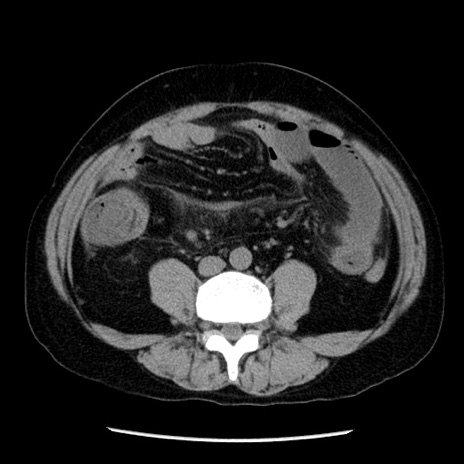

冠状断像

【症例】40歳代男性

【現病歴】2日前から胃痛あり。徐々に周期的な激痛に変化した。本日になっても激痛があるため受診。

【身体所見】意識清明、BT 38-39℃台あり、腹部:膨満、やや硬、右下腹部に圧痛あり。

【データ】WBC 8500、CRP 23.26